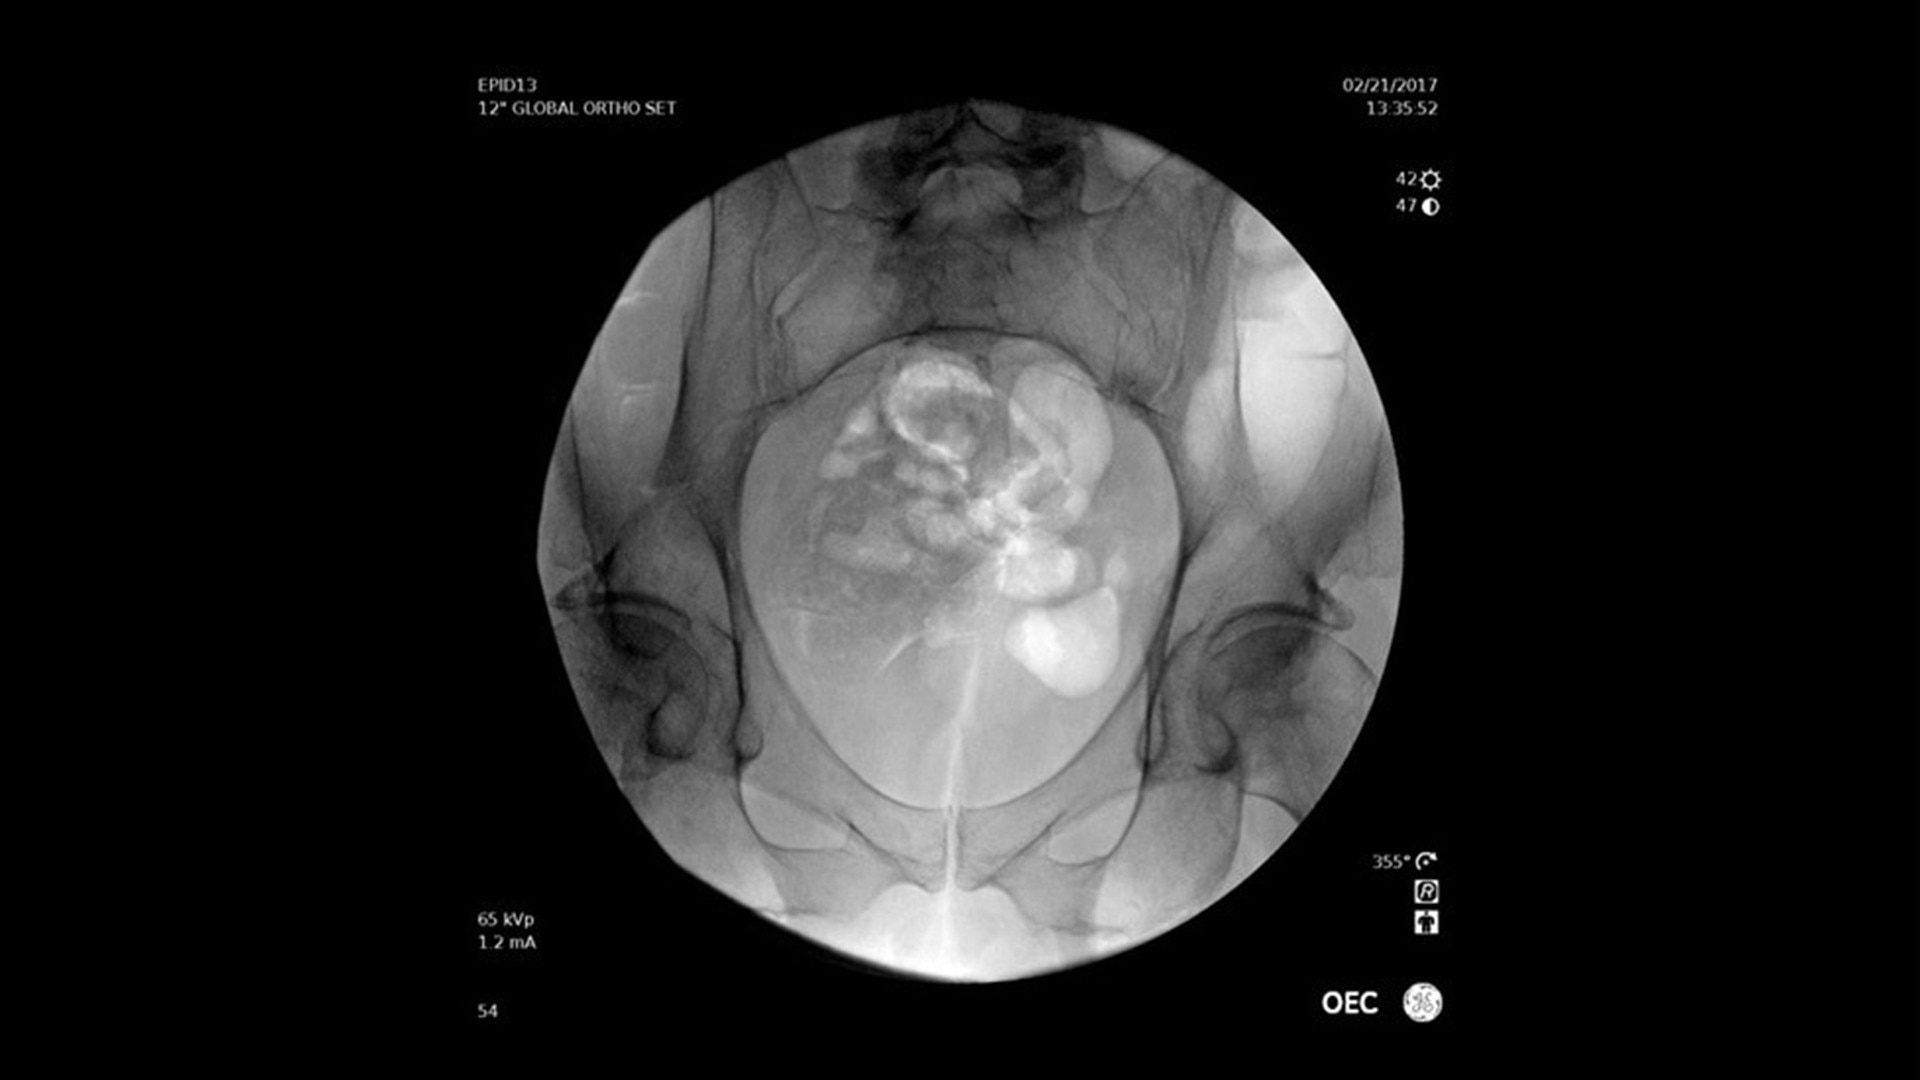

OEC Elite

Renommierte Bildqualität mit verbesserter Benutzerfreundlichkeit und Effizienz.

Der mobile C-Bogen OEC Elite unterstützt Sie mit leistungsstarker Technologie und intuitiver Bedienung – für mehr Effizienz in unterschiedlichsten chirurgischen Anwendungen. Profitieren Sie von:

• Hervorragender Bildqualität für präzise intraoperative Entscheidungen

Vielseitig einsetzbar – ideal für orthopädische, gastrointestinale, endoskopische, urologische, neurologische und vaskuläre Eingriffe sowie für die Intensiv- und Notfallmedizin.

Bildqualität und innovative Funktionen

Der OEC Elite unterstützt Ihr OP-Team mit fortschrittlicher Bildverarbeitung, die sich dynamisch an klinische Anforderungen anpasst. So entstehen jederzeit präzise und detailreiche Bilder.

Renommierte Bildgebung – mehr sehen, mit weniger Dosis.

Nutzen Sie innovative Funktionen wie Live-Zoom, Digital Pen und vorkonfigurierte Bildprofile – darunter Pädiatrie, General HD und die optionale Bolus-Verfolgung – für eine präzise und schonende Bildgebung.

Im Vergleich zu herkömmlichen Monoblock-C-Bögen ermöglicht der OEC Elite eine bis zu 22 % größere Darstellung anatomischer Strukturen und eine nähere Positionierung des Detektors an der Patientenanatomie.